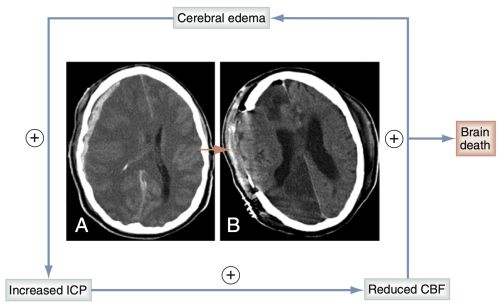

The vicious cycle of head injury

After severe TBI w/ ↑ ICP → ⊕ feedback loop can ensue, leading ultimately to brain death.

↑ of ICP (A) → impedes CBF → ischemia → cytotoxic edema caused in part by ATP–dependent Na+-K+ pump failure.

This in turn further ↑ ICP & ↓ CBF.

This situation can ultimately progress to brain death if ICP becomes so high that the cerebrum is not perfused.